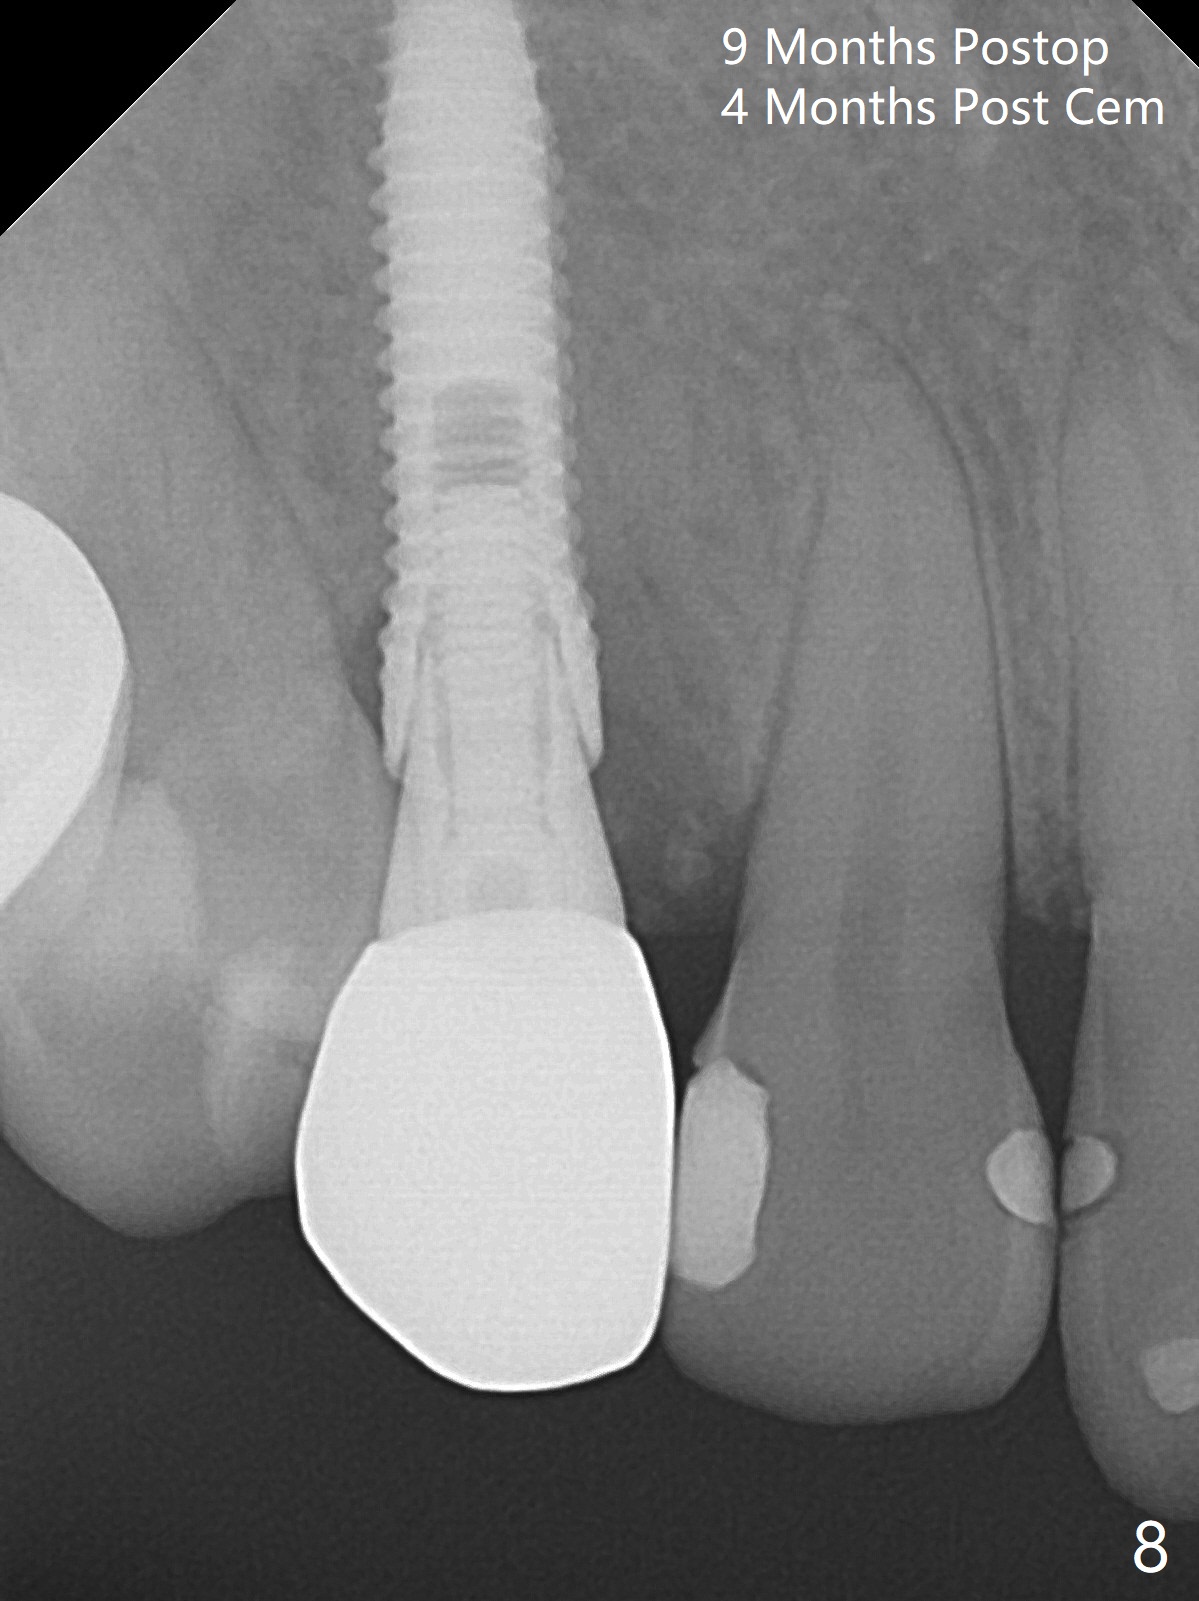

When the tooth #6 with loose crown and post (Fig.1) is extracted, there is no granulation tissue in the socket with the thin intact buccal plate. As planned, osteotomy is initiated in the mesio-palatal slope of the socket (Fig.2 red dashed line). After osteotomy for 3x20 mm (gingival level), a 3.8x15 mm dummy implant is placed partially (Fig.3 D). A final implant with the same dimension is placed with > 50 Ncm (Fig.4). Before and after placement of a 4.5x5(3) mm abutment, Vera graft is placed in the remaining socket space (mainly buccal, Fig.5 *). As routine, an immediate provisional is fabricated with occlusal clearance. The gingiva looks healthy around the provisional 1 week postop (Fig.6 P). Adjust and polish the mesioocclusal composite at #5 if necessary before impression. The bone graft appears to remain in place 4.5 months postop (Fig.7). A bevel buccal subgingival margin is placed prior to impression. The bone density around the coronal portion of the implant increases 9 months postop (4 months post cementation, Fig.8). There is no gingival erythema or edema around the implant crown at #6 ten months post cementation (Fig.6, as compared to preop condition and that of the neighboring crown (*)). Both the buccal and palatal plates are thin or absent 1 year 5 months post cementation (Fig.10,11, as compared to Fig.12 for the tooth #11 (thin buccal bone)). Socket shield should be done with a smaller implant.